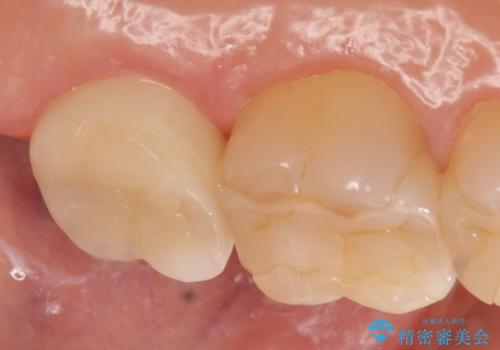

- 左上7が欠けてしまったので診て欲しいといらっしゃった方の症例です。

虫歯を除去後、オールセラミッククラウンによる補綴を行いました。

今回用いたオールセラミッククラウンは、ジルコニアフレームという白い素材の上にセラミックを盛っているため審美性が非常に高いのが特徴です。

またジルコニアは人工ダイヤモンドの材料にも使われているほど高い強度を持っており、そのためオールセラミッククラウンは審美性だけでなく、奥歯やブリッジの補綴も可能とするクラウンです。